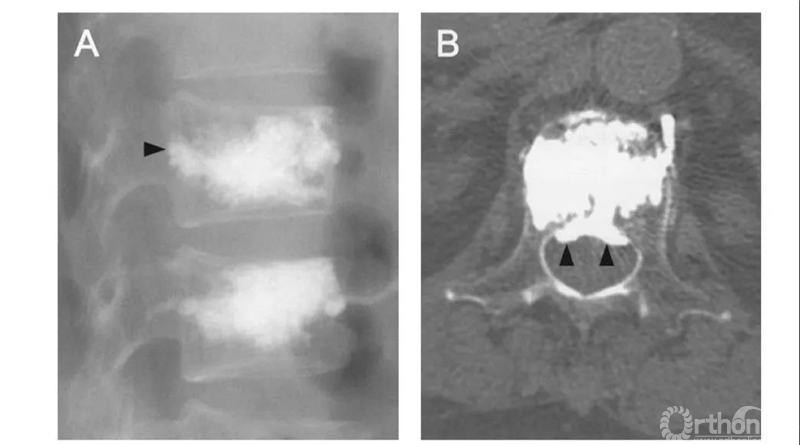

侧位X片看骨水泥在椎间孔周缘,CT显示渗漏进入椎管,累及椎间孔。